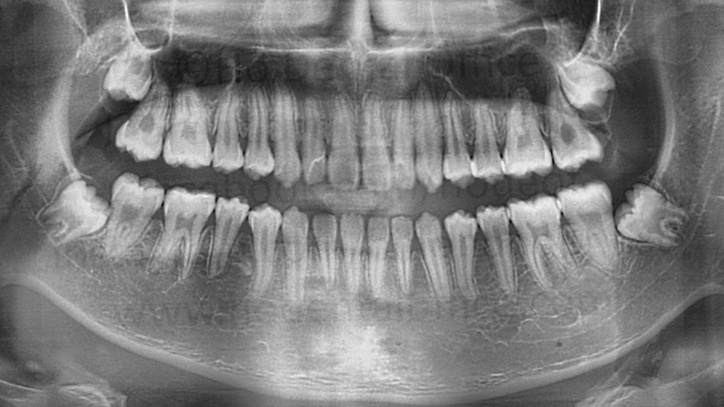

- prevention of difficult third molar extraction - Immature impacted third molars are easier to remove than fully grown ones! Third molars usually come out almost fully matured by the age of 18. Extracting it prior to that age would be easier since the tooth hasn't fully formed yet. Furthermore, the position of the third molar might transform to a more difficult position for extraction as the tooth matures and the patient ages.

![]() |